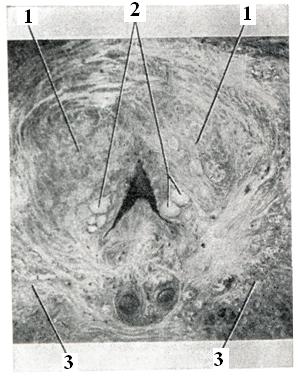

В предстательной железе в практическом отношении принято различать: верхнюю, или переднюю, — краниальную часть и нижнюю, или заднюю,— каудальную часть; с возрастом различие строения этих частей выявляется отчетливее (рис. 1 и 2).

Аденома развивается в краниальной части, а рак — в каудальной. Аденома и рак предстательной железы могут сосуществовать у одного и того же больного одновременно.

Эндоскопические методы исследования — цистоскопию, уретроскопию (см.) — следует проводить только при гематурии, подозрении на опухоль мочевого пузыря или для дифференциальной диагностики в неясных случаях. Уретроскопия показана в ранней стадии заболевания и не у пожилых, больных. При цистоскопии выявляются выбухания переходной складки в виде занавески (рис. 9), определяется средняя доля в виде барьера, уточняется наличие камней и сопутствующих заболеваний — цистита, язвы, папилломы. Во II и III стадиях заболевания цистоскопия затруднительна, может быть причиной развития инфекции, возникновения простатита и эпидидимита. Поэтому в последние годы большинство урологов предпочитает проводить цистоскопию в операционной перед операцией.